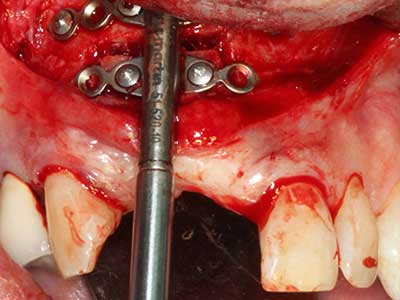

Piezo surgery has additional advantages when harvesting bone blocks. In addition to the high precision with osteotomy described above, the use of the thin saw tips specifically minimizes loss of material. Greater loss of material during harvesting can be expected with the thicker instrument tips, particularly when using Lindemann drills (Lakshmiganthan, Gokulanathan et al. 2012). The basal separation, which is necessary particularly for retromolar block transplants, is simplified by specially designed rectangular saws, with the result that piezo surgery is viewed as a precise, simple and safe procedure for harvesting retromolar bone blocks (Happe 2007) (Fig. 1-12).